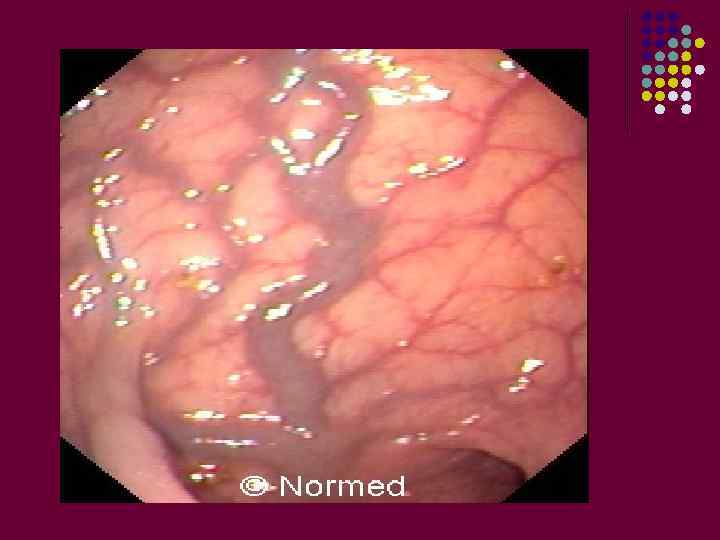

ПОРОКИ РАЗВИТИЯ ПОВЕРХНОСТНЫХ ВЕН Врожденные флебэктазы расширенные и извитые вены, внешне напоминающие варикозные.

Врожденные флебэктазы

Заболевание начинается в первые месяцы после рождения ребенка. Обычно вены локализуются на конечностях. Флебэктазы - меняют геометрию конечности, кожные покровы истончаются, становятся синюшными. Внешне при наполнении сосудов конечность становится ощутимо толще, чем другая. При пальпации таких вен - они легко спадаются и вновь наполняются кровью. При поднятии конечности она уменьшается в объеме. В состоянии наполнения причиняет неудобства и боли.

Как правило, венозные мешки располагаются вне основных венозных магистралей, и могут быть как в поверхностных тканях, так и в глубоких. Наряду с венозной патологией, страдает трофика других тканей, отмечается гипоплазия мышц, костей, замедляется их рост. Переполненные вены могут рваться. Прогрессирование болезни может приводить к язвам.